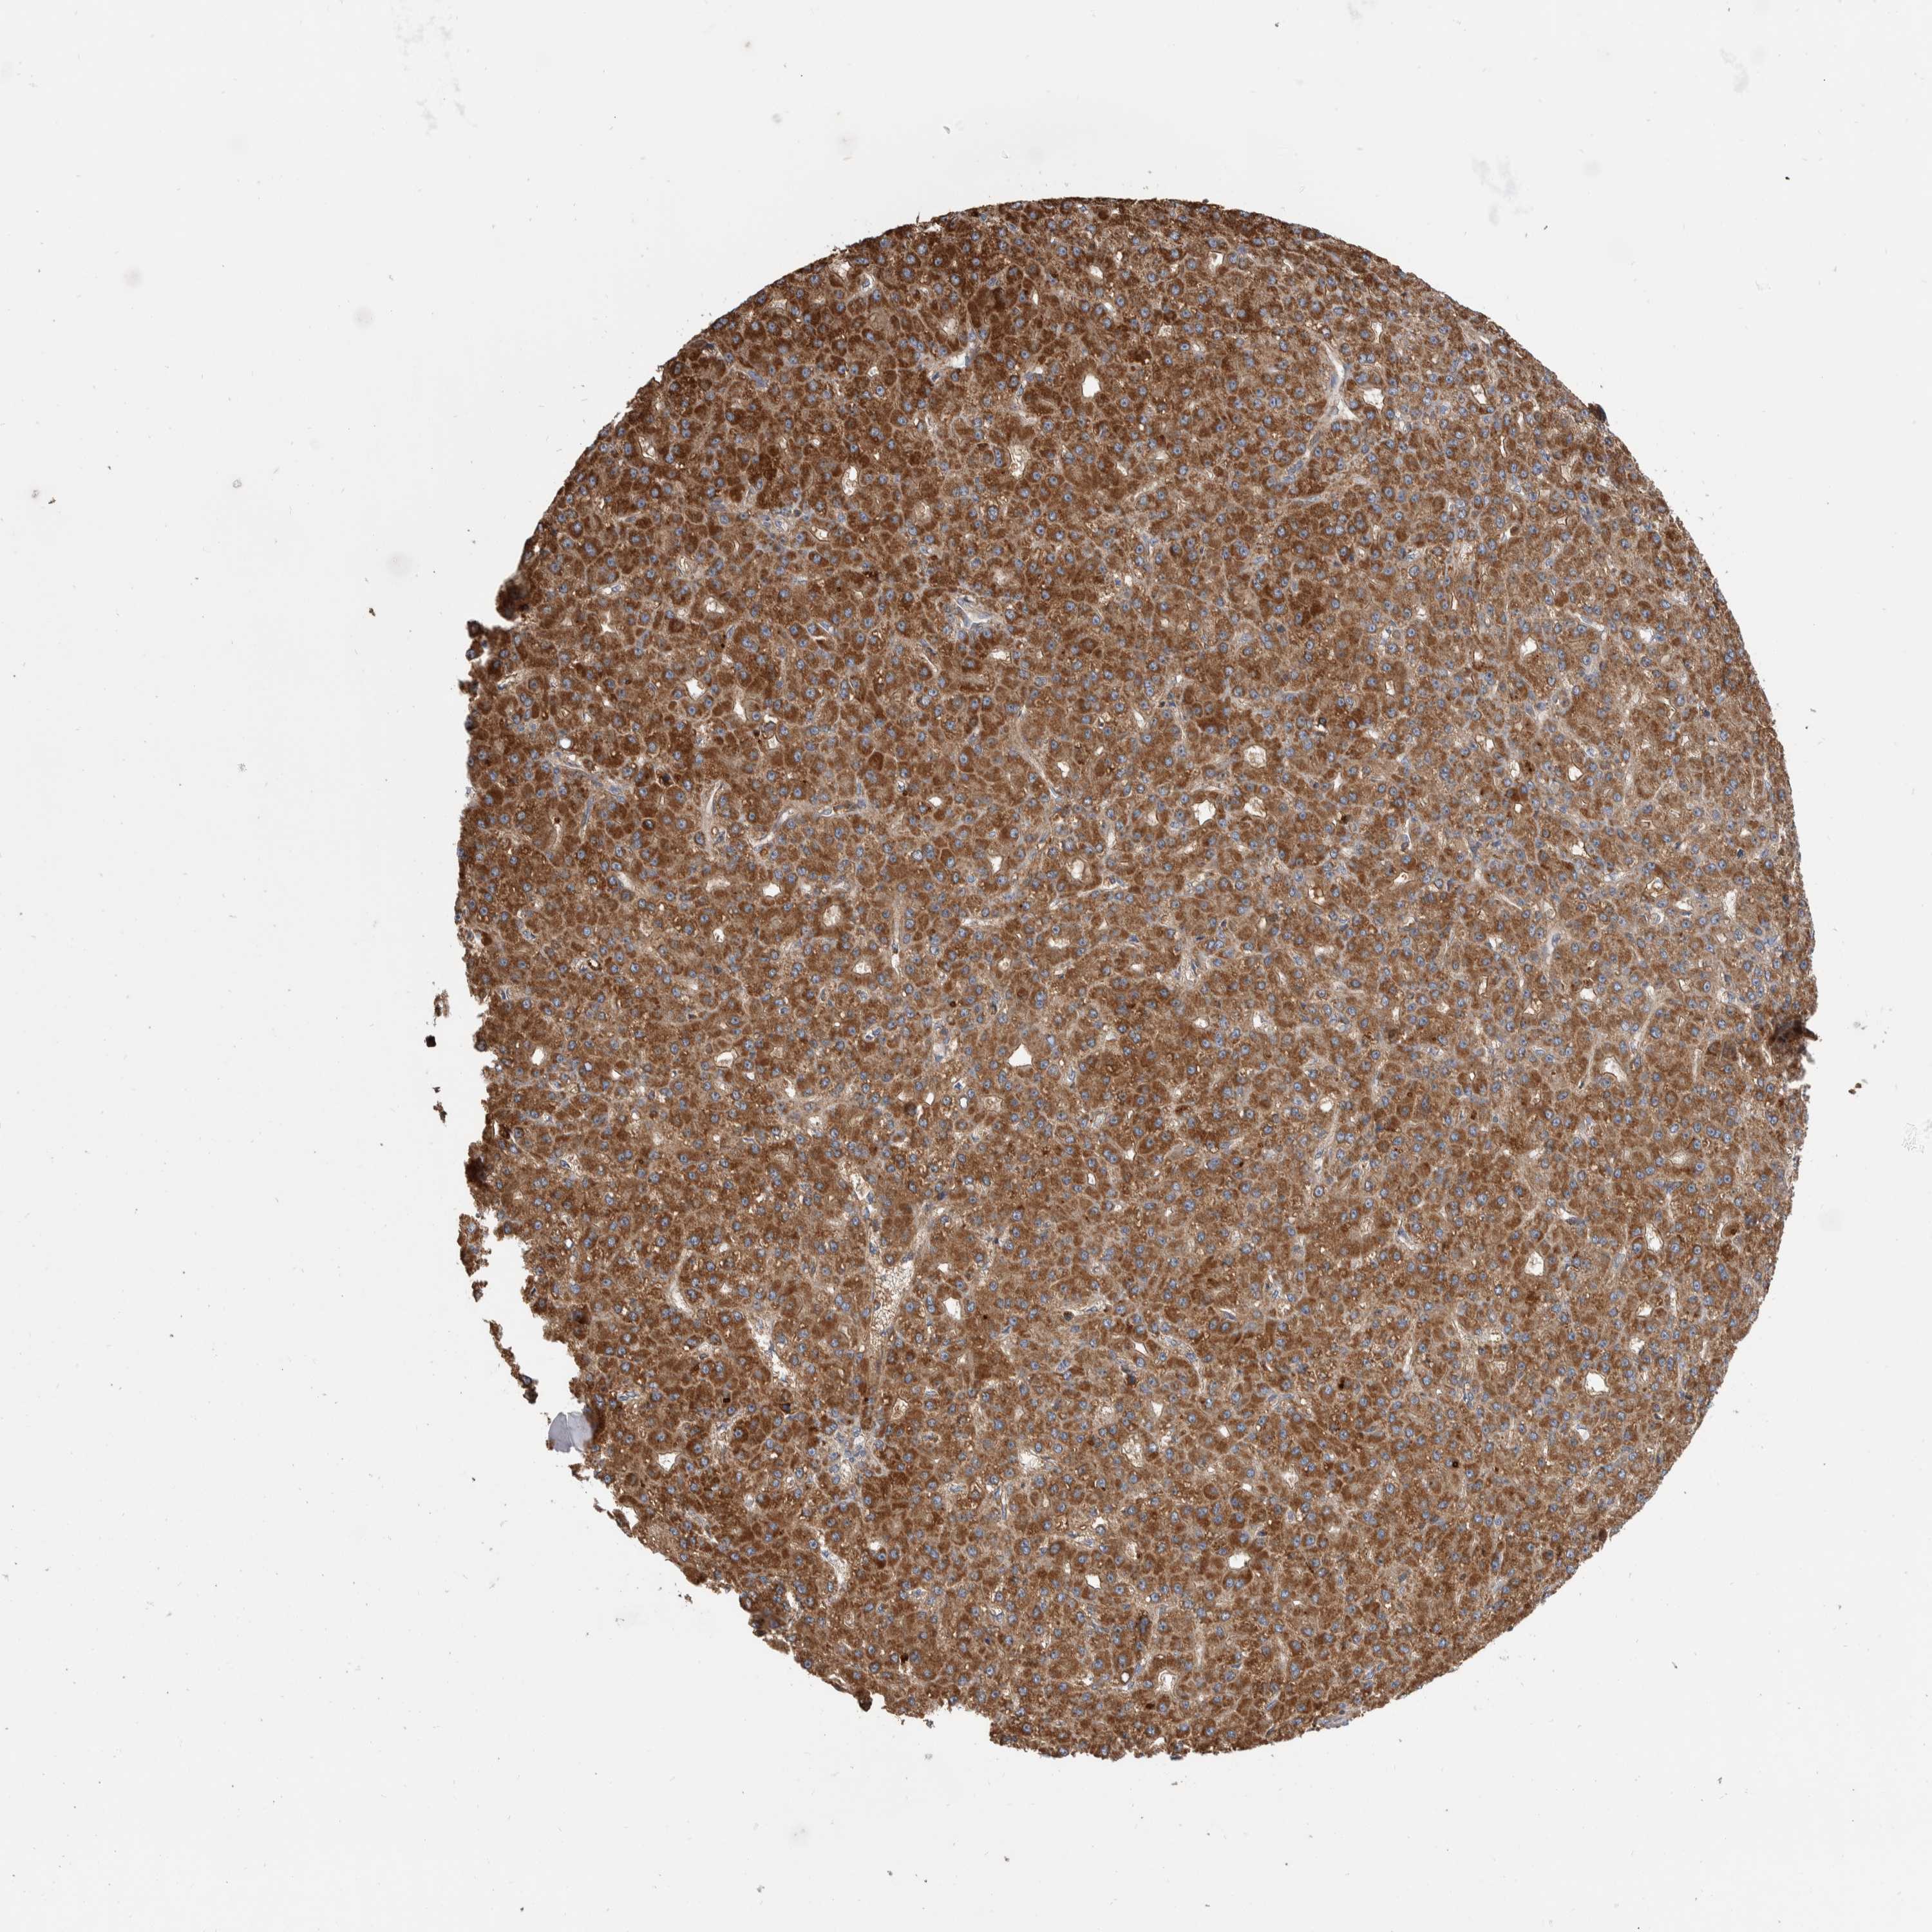

LIVER CANCER - Protein expressioni

A mouse-over function shows sample information and annotation data. Click on an image to view it in a full screen mode. Samples can be filtered based on level of antibody staining by selecting one or several of the following categories: high, medium, low and not detected. The assay and annotation is described here.

Note that samples used for immunohistochemistry by the Human Protein Atlas do not correspond to samples in the TCGA dataset.

Antibody stainingi

Antibody staining in the annotated cell types in the current human tissue is reported as not detected, low, medium, or high, based on conventional immunohistochemistry profiling in selected tissues. This score is based on the combination of the staining intensity and fraction of stained cells.

Each image is clickable and will lead to virtual microscopy that enables deeper exploration of all samples and also displays staining intensity scores, fraction scores and subcellular localization as well as patient and tissue information for each sample.

Antibody HPA023840

Antibody CAB012245

Staining

High

Medium

Low

Not detected

Intensity

Strong

Moderate

Weak

Negative

Quantity

>75%

75%-25%

<25%

None

Location

Nuclear

Cytoplasmic/membranous

Cytoplasmic/membranous,nuclear

Cholangiocarcinoma

Carcinoma, Hepatocellular, NOS